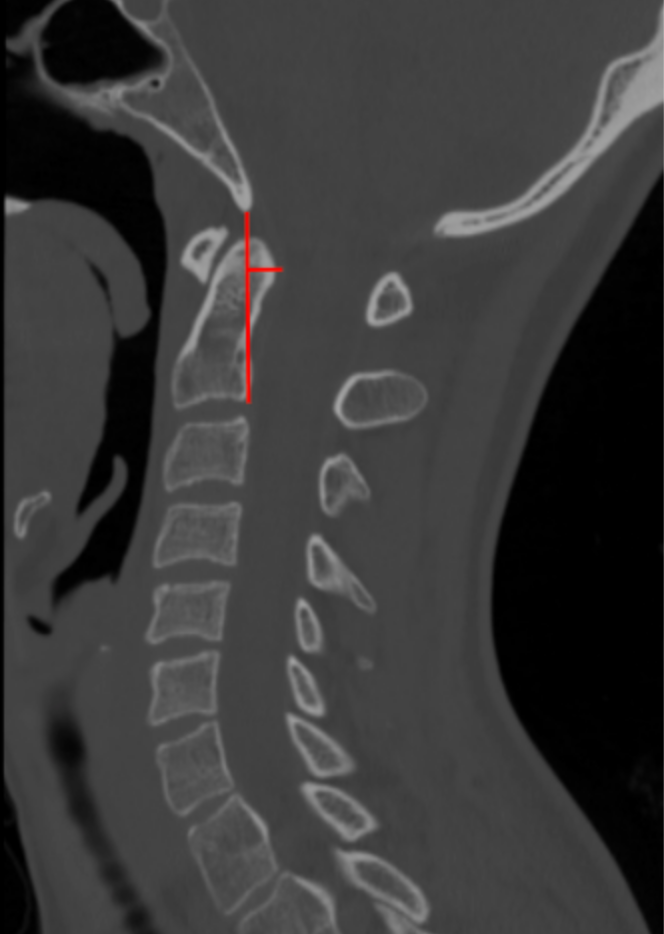

The Grabb–Oakes measurement, also referred to as the pB–C2 line, quantifies the degree of ventral brainstem compression at the craniovertebral junction. It measures the perpendicular distance from the posterior surface of the odontoid or ventral soft tissue mass to a reference line drawn between the basion and the posteroinferior aspect of the C2 vertebral body.

• Select a true mid-sagittal CT reconstruction that clearly visualizes the basion, odontoid process, and C2 vertebral body.

•  Draw the pB–C2 reference line:

• Draw a straight line connecting the basion to the posteroinferior aspect of C2.

• Identify the point of maximal ventral encroachment:

• Usually the posterior surface of the odontoid or associated retro-odontoid soft tissue.

• Draw a perpendicular line from the pB–C2 reference line to the point of maximal ventral encroachment.

• Measure this perpendicular distance in millimeters (mm).

This value is the Grabb–Oakes (pB–C2) measurement.